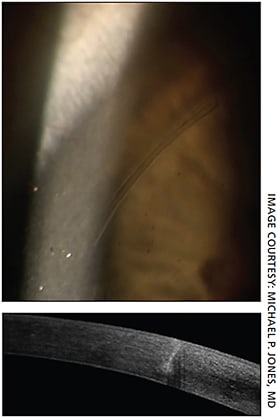

Using equipment like a Pentacam can have an additional benefit of not relying on an estimate of PCA and its effect on total corneal astigmatism — it will actually measure PCA directly. Using Pentacam PCA measurements with LENSAR femtosecond laser at the time of cataract surgery will allow the surgeon to perform arcuate incisions based on the PCA measurement. The downside of these devices is that they require equipment purchase, which may be out of reach for some practices.

Patients who have a total corneal astigmatism of less than 0.75 D can be dealt with using corneal incisions. Several nomograms are available for surgeons to follow, including LRIcalculator.com for handcut incisions and LaserArcs.com for femto-cut arcuate incisions. Femto-cut arcuate incisions have the advantage of being more predictable than handcut5 due to accuracy of placement and uniformity of depth. Platforms like Lensar or a Verion-coupled LenSx account for cyclorotation for added predictability. Also, femto incisions can be left closed and then opened at a later date to titrate any residual astigmatism as needed.